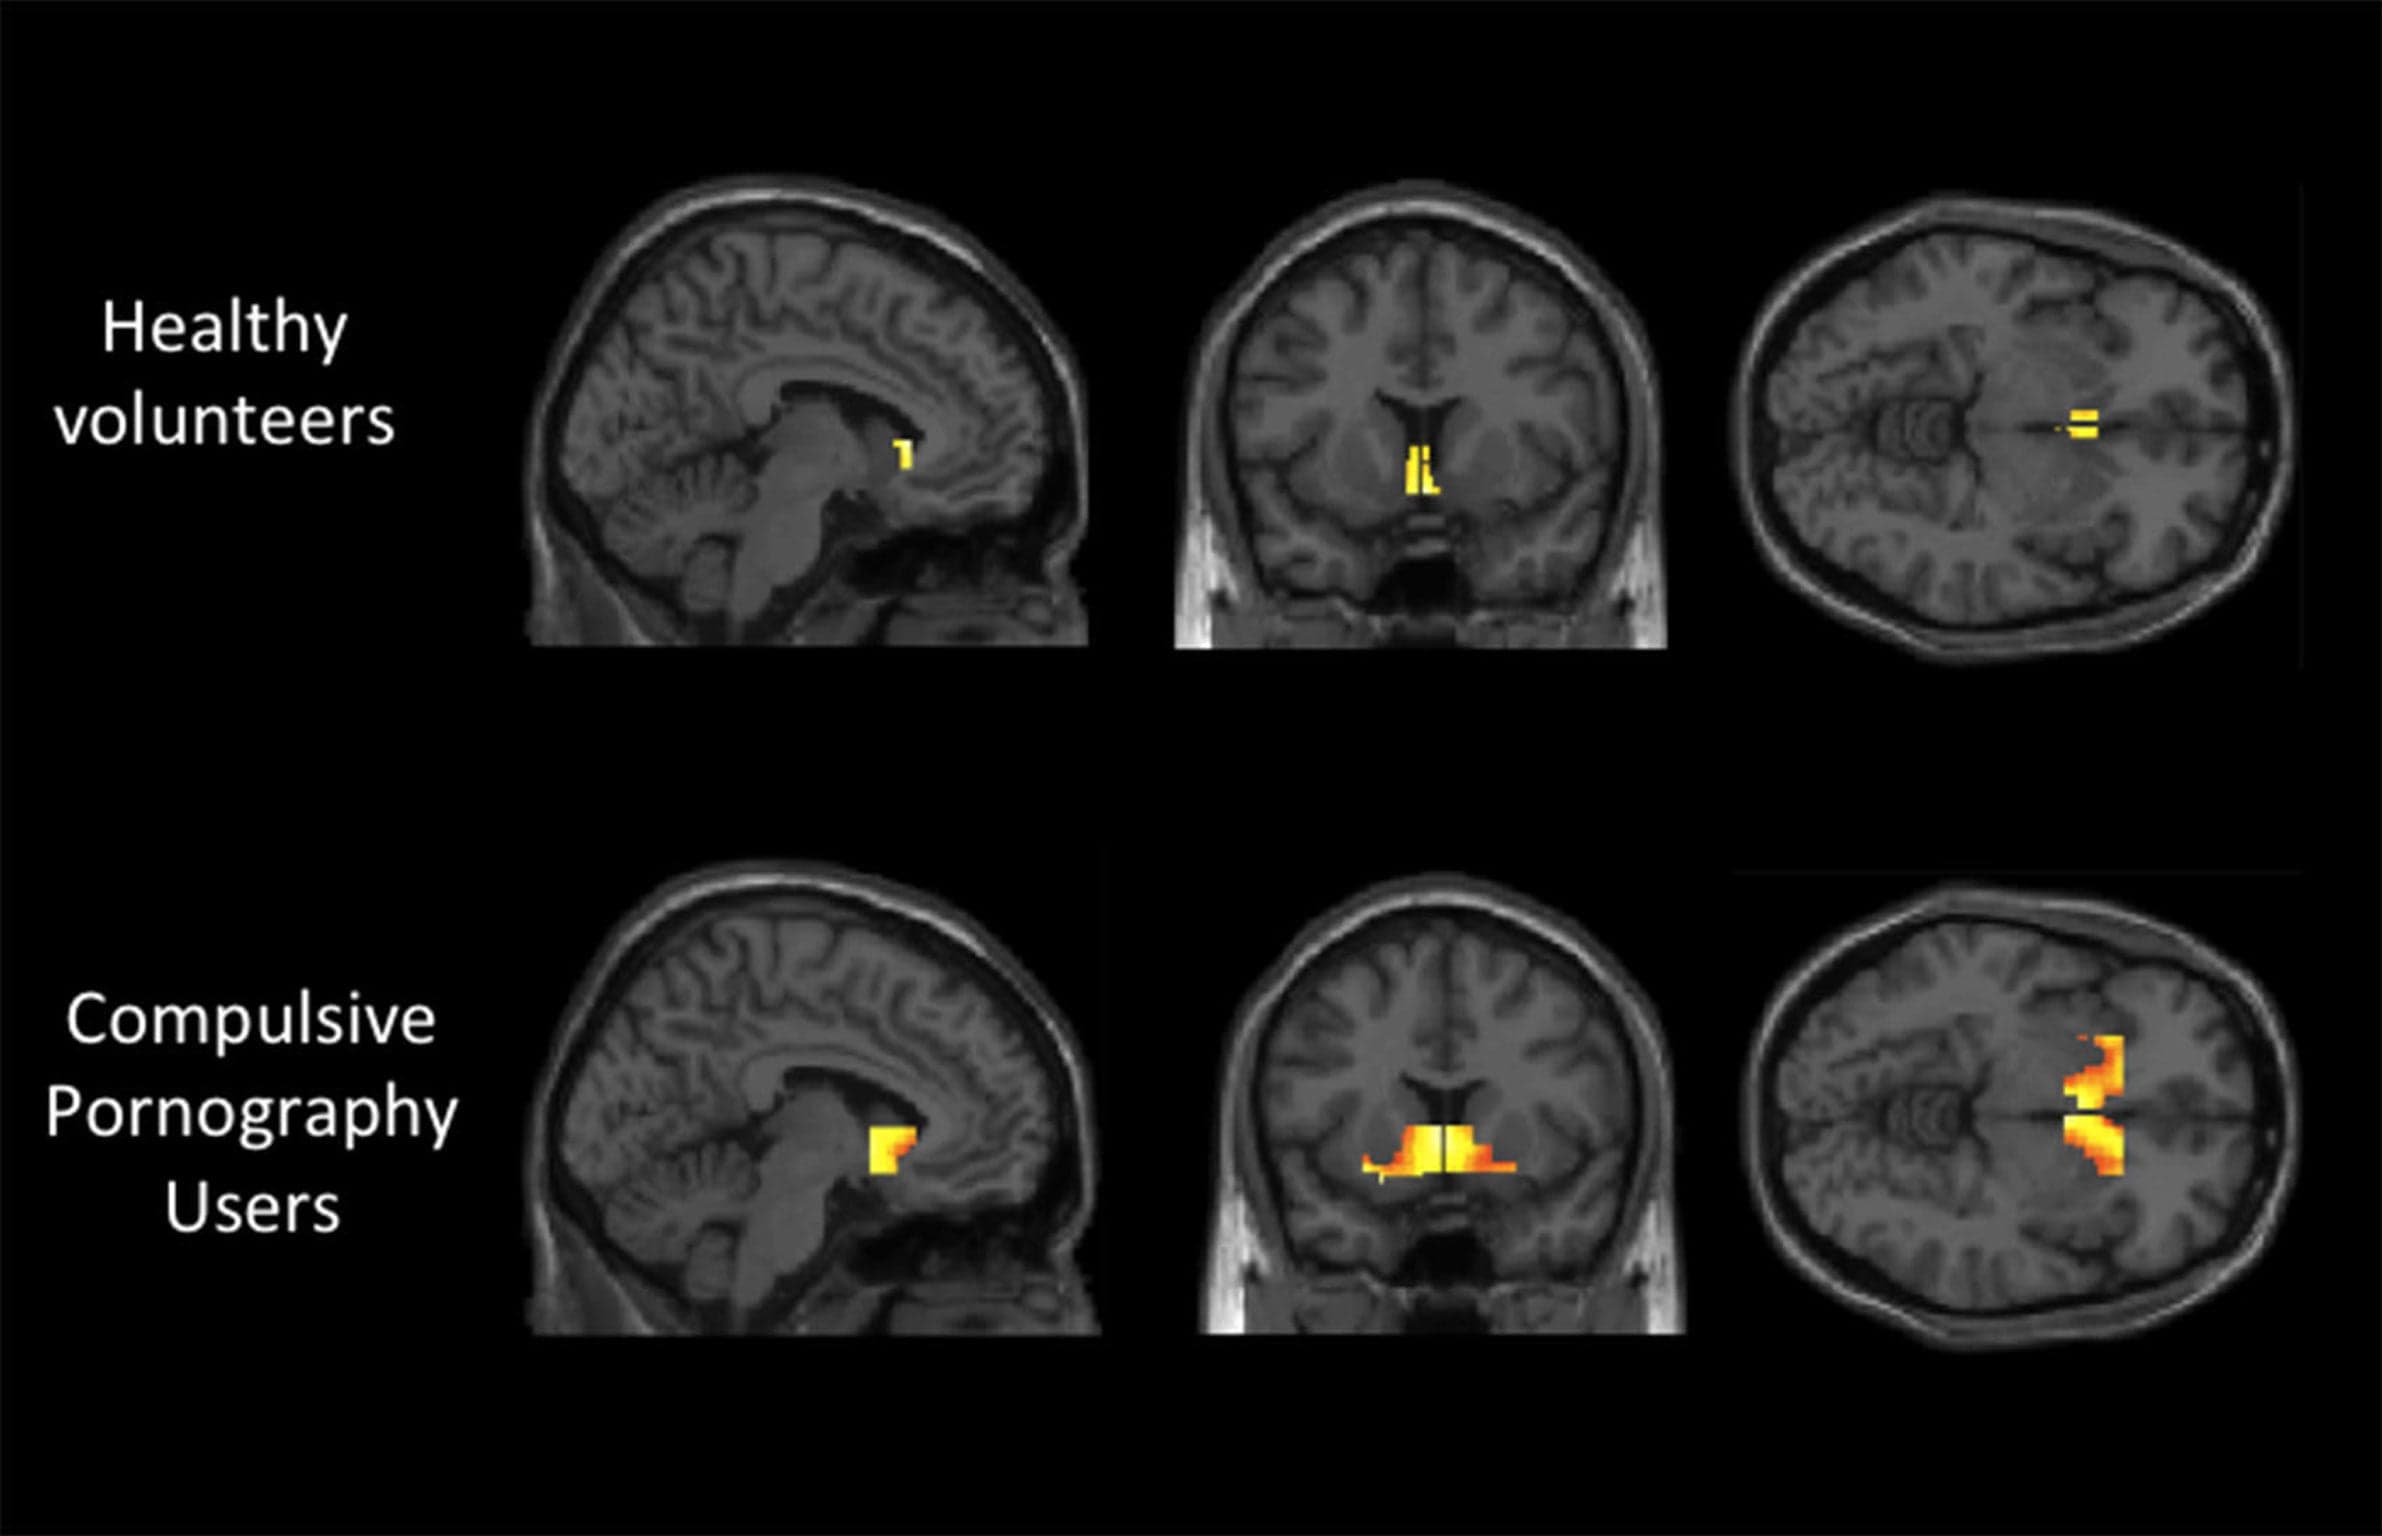

Neuroscientific studies have investigated the brain's response to pornography, with some findings indicating similarities to drug addiction. Dr. Valerie Voon's research at the University of Cambridge, for instance, found that brain activity in individuals with compulsive sexual behavior mirrored that seen in drug addicts when exposed to relevant stimuli. These studies often highlight the activation of reward pathways involving dopamine, suggesting that problematic pornography use can lead to sensitization and craving, where individuals "want" more despite not necessarily "liking" it, a phenomenon also observed in drug addiction.